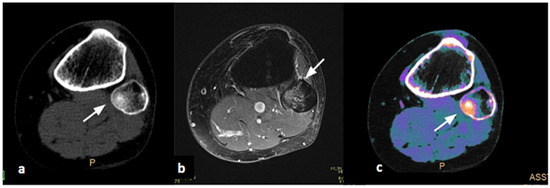

Figure 1. Female, 61 years old, sprain injury. (a) Axial CT image, baseline acquisition of the knee, does not show cortical alterations (white arrow). (b) Axial MRI acquisition demonstrates edema of the fibular head in PD/T2 FAT-SAT, indicating acute post-traumatic interstitial hemorrhage (white arrow). (c) Axial Dual-Layer Spectral CT (DL-SCT) image, post-processed with the IntelliSpace software, shows the presence of edema through an increase in electron density (ED) visible with orange coloring (white arrow). Color bar legend. White: normal cortical bone; orange: intermediate to high ED; purple: low ED; blue: very low ED, consistent with normal bone marrow composition rich in fat.